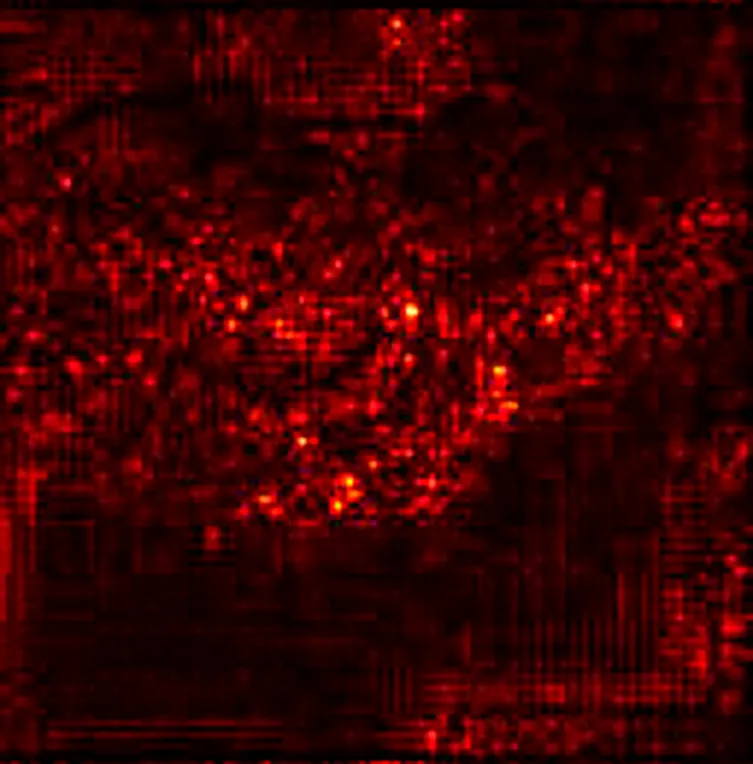

Additionally, Figure 1 below presents a sample of ultrasound images from each of the three classes, demonstrating the visual differences between the conditions and the challenges involved in classification.

Figure 1

www.frontiersin.org

Figure 1. Sample ultrasound images from the dataset, representing the three classes: (a) Normal, (b) Dominant Follicle, and (c) Polycystic Ovary Syndrome (PCO). These examples highlight the visual differences between the classes used for muticlass classification.

To further enhance interpretability, we selected one representative test image from each class—Normal, PCO, and Dominant Follicle—and analyzed the predicted class probabilities output by each model. Alongside each sample image, we also provide its corresponding Grad-CAM saliency map based on the best-performing model (ResNet18), which highlights the image regions that influenced the model’s decision. Table 7 presents these results, showing the image, its saliency visualization, and the predicted probabilities assigned by each model. This multimodal view helps illustrate how confidently and consistently each model responds to different ovarian conditions.

Table 7

Table 7. Predicted probabilities for representative images of each class across all models. Values are ordered as Normal, PCO, Dominant Follicle. Grad-CAM maps are from ResNet18.

To support model interpretability, we incorporated Grad-CAM visualizations using the best-performing architecture (ResNet18). These visual explanations highlight the specific regions of ultrasound images that influenced the model’s predictions, helping clinicians understand the basis of the classification. By providing visual cues linked to diagnostic decisions, such methods can improve trust in AI systems and facilitate their integration into clinical workflows. As shown in Table 7, combining probability outputs with saliency maps offers a more transparent view of model behavior across different ovarian conditions.